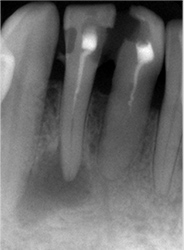

こちらのレントゲン写真を見てください。どちらかの歯医者さんで神経を取っています。根管に入れる薬は白く映ります。赤矢印部分です。一番右側が模式図ですが、青い部分が薬、根っこの先の赤点が化膿している部分です。

薬がほとんど入っていないのがわかります。黄矢印部分です。青矢印まで薬が入らないといけないのですが、全く入っていません。その結果、根っこの先が黒くなっています。膿が貯まって化膿すると黒く写ってくるのです。

別な歯科医院で治してもらいました。薬が根の先まで入っているのがわかります(黄矢印)。 根尖の黒い影が消失しています(赤矢印)。骨が再生すると白く写るようになります。

①の写真はどちらかの歯医者さんで神経を取ってもらったレントゲン写真です。根っこの中に薬が全く入っていません。

②の模式図で青く描かれている部分が薬です。

根の先を見ると小豆ぐらいの大きさの黒い影が見えます。根の中でばい菌が繫殖し感染を起こすとこのような黒い影ができます。黒い影の部分は膿(ウミ)が貯まっています。こうなると腫れて痛みが出てくるのです。

③、④の写真はそれを治した後のレントゲン写真とその模式図です。白く映っている薬が根の先まできちんと入っているのが確認できます。そして根の先にあった黒い影が消えているのが分かります。根の先の炎症が治って、骨が再生すると白く映るのです。